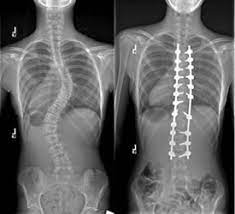

يطرح الطبيب المعالج خيار الجراحة عندما تكون درجة الانحناء أكثر من 45 درجة في مرحلة النمو او اكبر من 50 درجة في مرحلة ما بعد النمو

ويتم استخدام هذه الوسائل التعويضية من أجل تصحيح العمود الفقري وتثبيت الفقرات في الوضعية الصحيحة حتى يصبح بالإمكان إجراء عملية لحام للفقرات في كتلة عظمية واحدة.